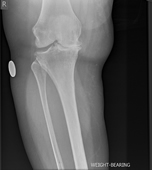

Knee replacement involves replacing the worn out knee joint. The end of the femur is resurfaced with a metallic component, a tray is placed on the tibia and a polyethylene spacer is inserted between the two components. For most total knee replacement the under surface of the kneecap is re-surfaced with a small polyethylene button.

In contrast to the hip joint the knee joint is made up of three parts or compartments. The inner (medial) and outer (lateral) halves and the patello-femoral joint (knee cap), it is possible to replace these separate components in isolation, depending of the type and pattern of arthritis the patient has.